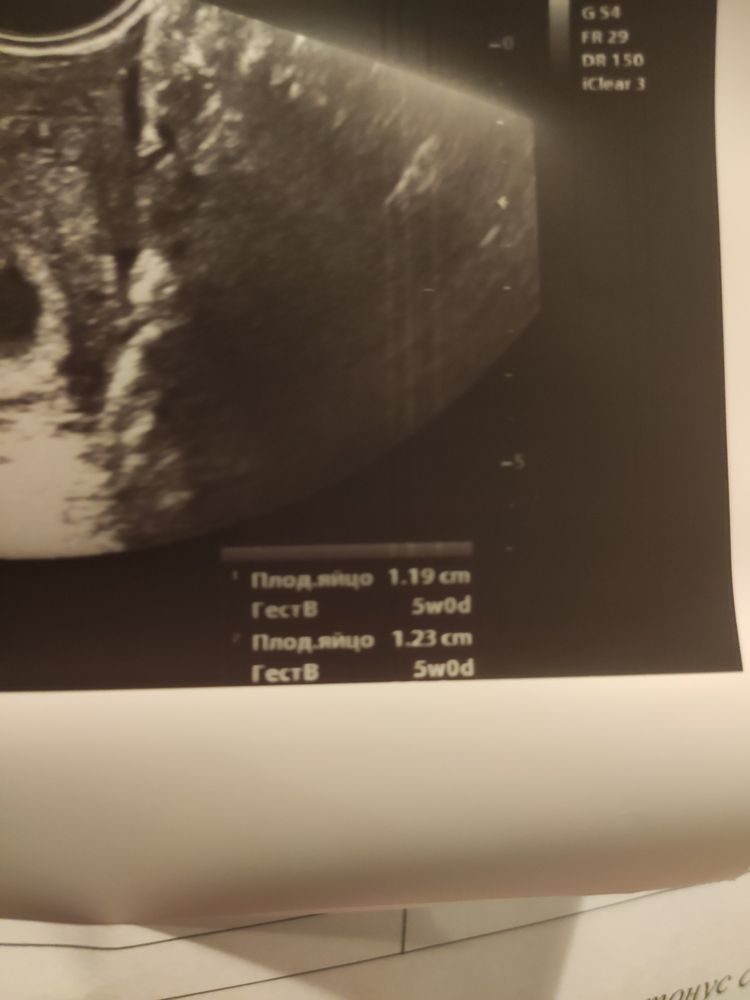

Девочки, здесь же норм все для 5 АК недель?